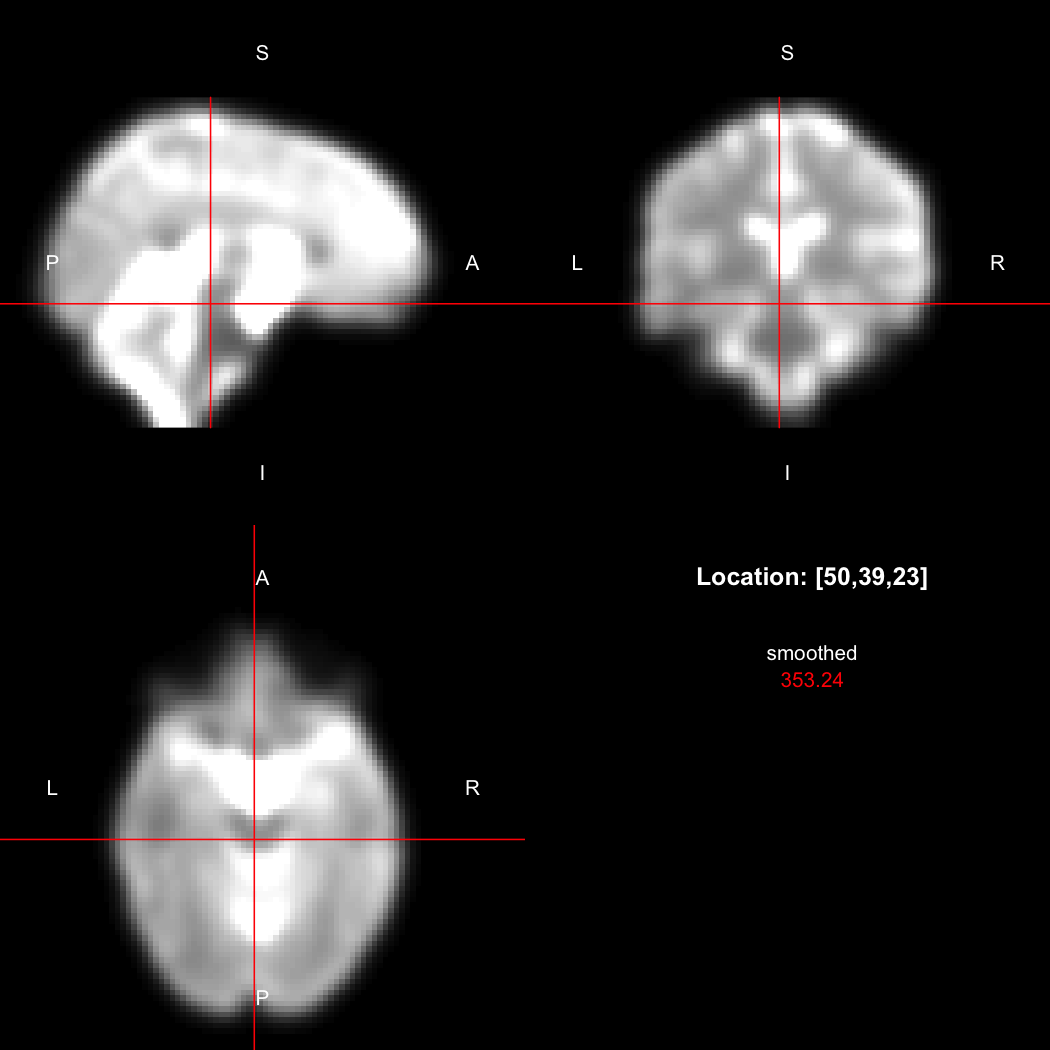

A simple example operation would be to smooth the image with a Gaussian smoothing kernel of standard deviation 4 mm. We can use standard R syntax to perform this operation, return a result, and then show it:

smoothed <- run(smooth_gauss(image, 4))

view(smoothed)

## Setting window to (0, 549.9)

Here, smooth_gauss() requests the smoothing operation,

and run() actually runs the pipeline and returns the

processed image.

However, the pipe syntax provides an alternative, which can be

further simplified because calling view() on a pipeline

will implicitly run it.

image %>% smooth_gauss(4) %>% view()

Notice now smooth_gauss() is now called with only one

argument, and view() with none, because the input to the

pipe (%>%) is implicitly added first. The benefits to

readability of this approach increase substantially as more operations

are added to the chain: